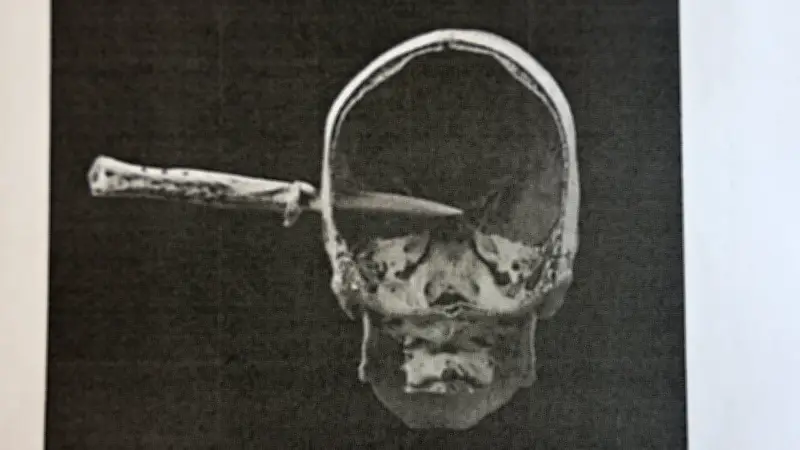

Vor dem Landgericht Görlitz wurde Tony B. (35) wegen Mordes an Steven M. (30) zu lebenslanger Freiheitsstrafe verurteilt. Der Vorsitzende Richter zeigte im Prozess ein Foto der Rechtsmedizin, das das im Schädel steckende Messer dokumentierte. „Ich werde die Strafe annehmen, wie sie kommt“, waren die letzten Worte des Angeklagten vor der Urteilsverkündung.

9,4 Zentimeter tief im Schädel

Die 9,4 Zentimeter lange, spitze Klinge drang komplett in den Schädel ein und blieb stecken. Steven M. wurde in die Uniklinik Dresden geflogen, wo er an seinen schweren Verletzungen verstarb. Die Eltern des Opfers traten im Mordprozess als Nebenkläger auf.